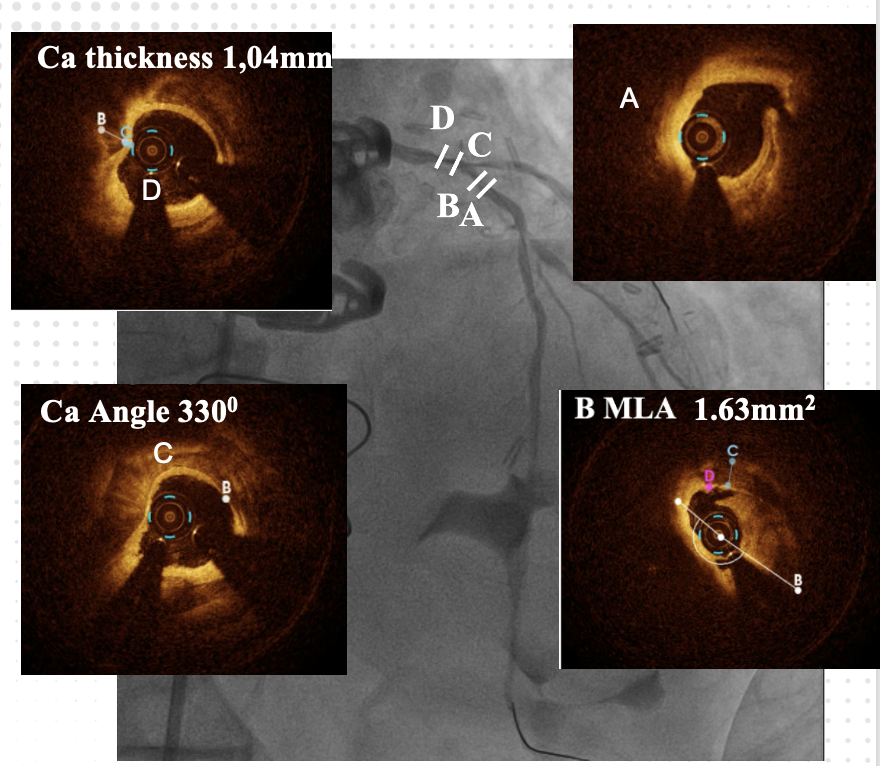

At the 1st encounter, RCA CTO PCI was performed with a plan for staged PCI of the left system. Using a 7F AL 0.75 for strong support, an antegrade approach with a double-lumen microcatheter and parallel wire technique (Pilot 150) successfully crossed the lesion. Predilatation with a 1.5 ¡¿ 15 mm balloon was done. IVUS could not pass due to 360¡Æ calcification. Rotablation with a 1.25 mm burr was attempted but limited to mid-RCA. Two DES were implanted from mid to proximal RCA, followed by post-dilatation.At the 2nd encounter, RCA stents were patent. PCI was done on LM, LAD, and D2. D2 was treated with DCB. LAD predilatation followed by OCT showed severe 330¡Æ calcification (max thickness 1.04 mm, MLA 1.63 mm©÷). IVL with a 2.75 ¡¿ 12 mm balloon (30 pulses) achieved multiple calcium fractures. A 2.75 ¡¿ 33 mm DES was deployed with good OCT results.At the 3rd encounter, 6 months later, the patient presented with ADHF. Angiography revealed RCA ISR CTO at the mid-bending site. The lesion was crossed with a Pilot 200 wire; predilatation showed a dog-bone sign. We do balloon based strategy for plaque modification using cutting, scoring, and double-wire balloons. IVUS showed stent underexpansion with 270¡Æ calcification and distal RCA stenosis. IVL with 2.5 and 2.75 mm balloons optimized the lesion, followed by two DES from distal to mid RCA. Post-PCI IVUS confirmed good result.